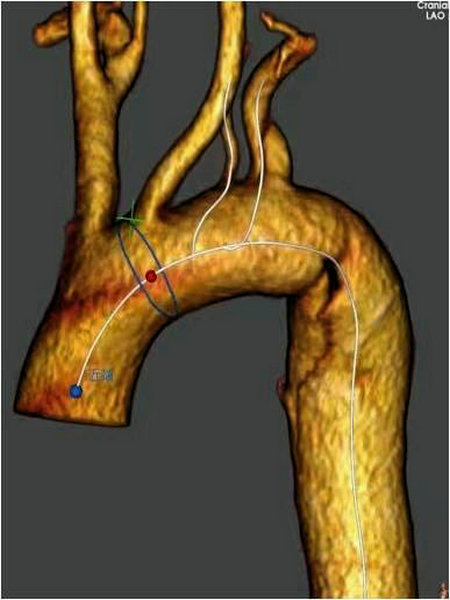

王颖主任团队研究讨论后决定目前治疗方案最可行的是胸主动脉覆膜支架腔内隔绝术,通过胸腹主动脉CTA提供的数据,该患者夹层破口紧贴左锁骨下动脉,并且先天血管畸形,他的左侧椎动脉由主动脉弓部分出,如使用传统直筒式覆膜支架,因支架锚定区不足需覆盖左锁骨下动脉,容易造成支架后循环缺血,甚至脑梗等风险,最终选用Castor®分支型覆膜支架联合体外开窗左椎动脉。在与麻醉科孙宝文主任及其团队、介入手术室、采购科等相关科室的紧密配合下手术如期进行。

术前准备:患者平躺后全麻,双侧腹股沟及左侧肱动脉术区消毒,对左侧肱动脉、左侧股动脉分别进行穿刺同时置入动脉鞘,游离右侧股动脉进行开口,沿股动脉入金标猪尾导管进入真腔至升主动脉,进行造影,位置与术前CTA检查结果一致。

体外开窗:打开支架前端,褪下部分外管和软鞘,放开前端部分主体支架,根据术前测量结果,在支架外标记左侧椎动脉开口完成体外开窗,将支架撤回软鞘和外管内。